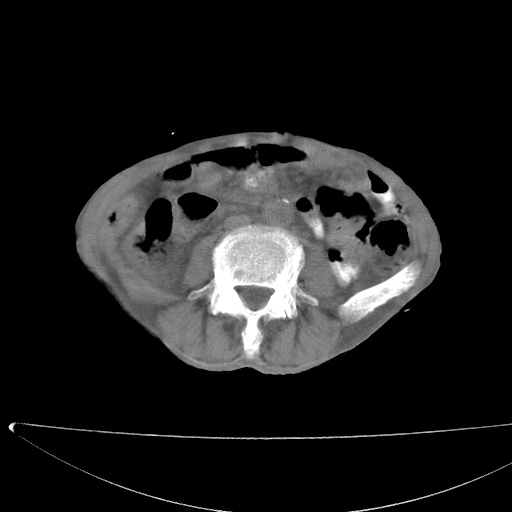

患者男70岁,上腹部不适1月。8年前有胃癌手术史。余病史不祥。

考虑胃癌复发并小网膜淋巴结转移侵及肝脏胆总管梗阻

考虑胃癌复发并腹腔内淋巴结转移。

1)胃癌术后,复发不排除。

2)肝脏转移瘤。

3)肝脏钙化灶。

4)胆囊增大。

5)腹膜后多发性淋巴结转移。

6)腹水。

建议:增强扫描。

考虑胃窦癌肝门转移

考虑胃癌复发并腹腔内淋巴结转移,胆总管受侵。

考虑胃窦癌肝门区淋巴结转移!

1)胃癌术后,不排除复发可能。2)考虑肝脏及腹膜后淋巴结转移瘤。3)肝内胆管扩张,胆囊增大。4)肝内胆管结石(或钙化)。5)脾脏钙化灶。6)腹水。7)右侧少量胸腔积液。

建议:行ct增强扫描检查。

1、胃癌根治胃空肠吻合术后,残胃癌?

2、肝门区占位性病变并胆道上段梗阻(肝内胆管扩张、胆囊增大),考虑肝门区淋巴结转移累及胆总管,建议ct增强扫描;

3、右侧胸腔少量积液、少量腹水;

4、肝右叶胆管结石。

肝门区占位性病变并肝内胆管扩张。

小网膜囊区及腹膜后肿大淋巴结。